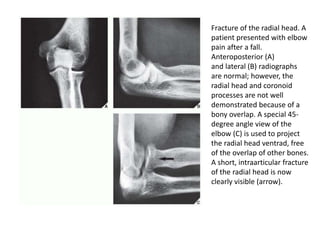

Fracture of the radial head. A

patient presented with elbow

pain after a fall.

Anteroposterior (A)

and lateral (B) radiographs

are normal; however, the

radial head and coronoid

processes are not well

demonstrated because of a

bony overlap. A special 45-

degree angle view of the

elbow (C) is used to project

the radial head ventrad, free

of the overlap of other bones.

A short, intraarticular fracture

of the radial head is now

clearly visible (arrow).